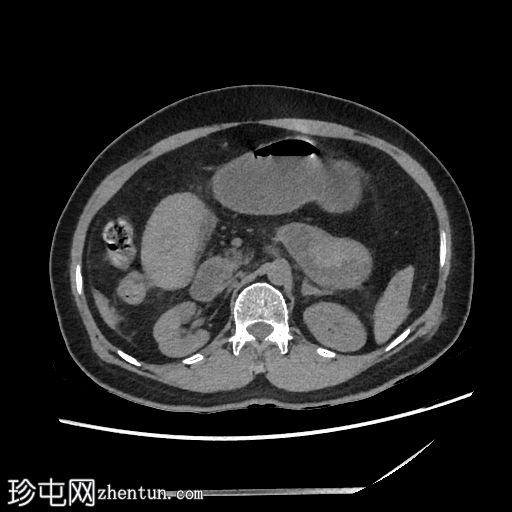

轴位增强

动脉期

肠壁强化减弱,高度提示肠缺血。

腹腔内可见中等量腹水。

低灌注综合征:

血管表现

腹主动脉管径变细:前后径12 mm

腹主动脉分支变细:腹腔干5.3 mm;肝总动脉3.2 mm;脾动脉1.5 mm;肠系膜动脉直径 4.4 mm

下腔静脉扁平征

内脏表现

脾脏灌注不足,脾脏体积略有缩小:初始测量值为 57 x 35 x 38 mm,后续影像学检查缩小至 56 x 31 x 33 mm

肝脏灌注不足:肝实质呈不均匀强化,主要累及右肝叶

双侧肾上腺强化

双侧可见肾图增高、延长且呈条纹状

影像学表现提示自发性空肠壁内出血,伴有肠壁缺血的证据,导致出血性休克和弥漫性血管痉挛。CT 扫描期间,患者正在接受血管加压药物支持。

红细胞计数:1,77。血红蛋白:54 克/升。红细胞压积:16.4%。

国际标准化比值:28.3。